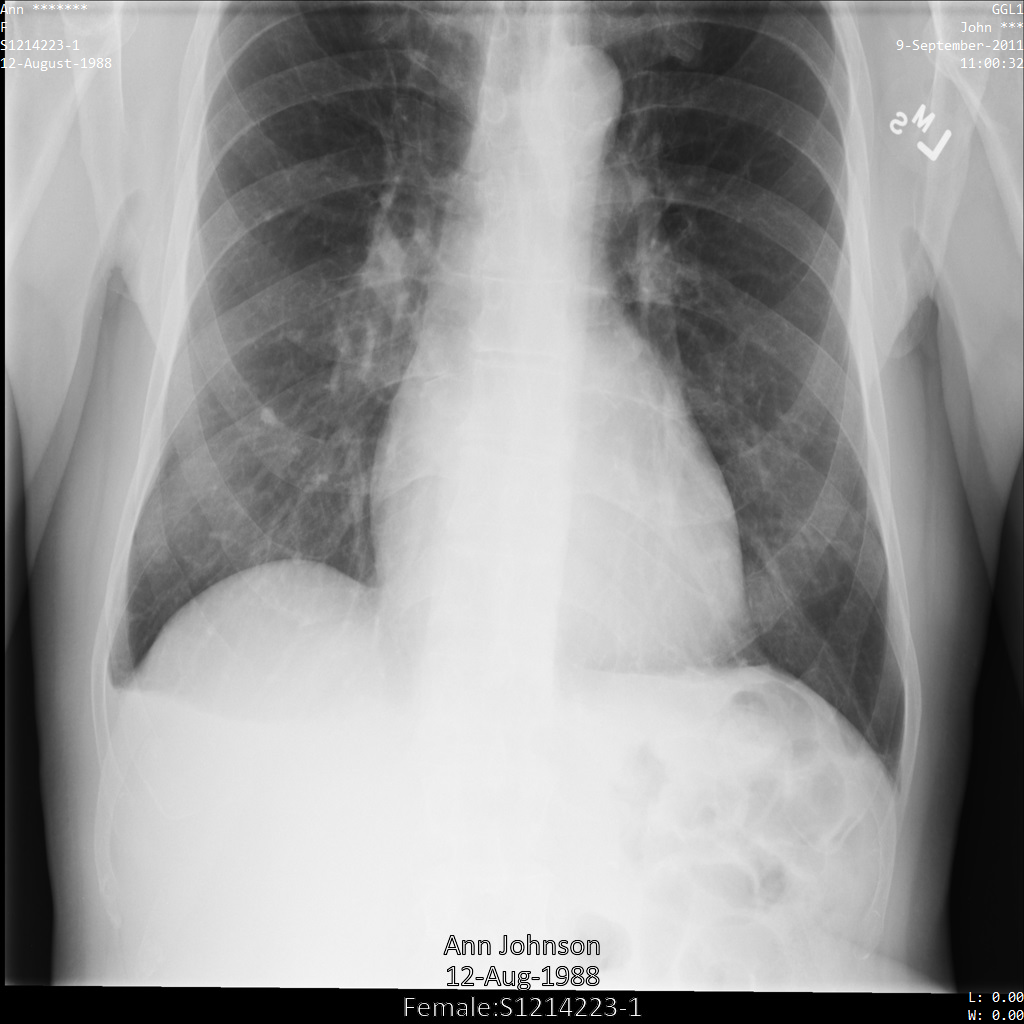

En cada una de las siguientes secciones, se proporcionan ejemplos de cómo desidentificar datos de DICOM mediante varios métodos. Se proporciona un resultado de la imagen desidentificada en cada muestra. En cada muestra, se usa la siguiente imagen original como su entrada:

Puedes comparar la imagen de salida de cada operación de desidentificación con esta imagen original para ver los efectos de la operación.

Después de enviar la imagen a la API de Cloud Healthcare, la imagen aparece de la siguiente manera. Mientras se ocultan los metadatos que se muestran en las esquinas superiores de la imagen, la información de salud protegida (PHI) quemado en la parte inferior de la imagen permanece. Para quitar también el texto quemado, consulta Oculta el texto quemado de las imágenes.

Después de enviar la imagen a la API de Cloud Healthcare, la imagen aparece de la siguiente manera. De las etiquetas proporcionadas en la removelist, solo se quita PatientBirthDate en la imagen, ya que es la única etiqueta de la lista de eliminación que corresponde a los metadatos visibles en la imagen.

Si bien PatientBirthDate en la esquina superior de la imagen se ocultó de acuerdo con la configuración de la removelist, la PHI de efecto quemado que se encuentra en la parte inferior de la imagen permanece. Para quitar también el texto quemado, consulta Cómo ocultar el texto quemado de las imágenes.

Después de enviar la imagen a la API de Cloud Healthcare mediante el perfil de filtro de etiqueta ATTRIBUTE_CONFIDENTIALITY_BASIC_PROFILE, la imagen aparece de la siguiente manera. Mientras se ocultan los metadatos que se muestran en las esquinas superiores de la imagen, permanece la PHI quemada que se encuentra en la parte inferior de la imagen.

Para quitar también el texto grabado, consulta Cómo ocultar el texto grabado de las imágenes.

Después de enviar la imagen a la API de Cloud Healthcare mediante la opción REDACT_ALL_TEXT, la imagen aparece de la siguiente manera. Mientras se quita el texto grabado en la parte inferior de la imagen, los metadatos en las esquinas superiores de la imagen permanecen. Para quitar también los metadatos, consulta Desidentifica las etiquetas de DICOM.